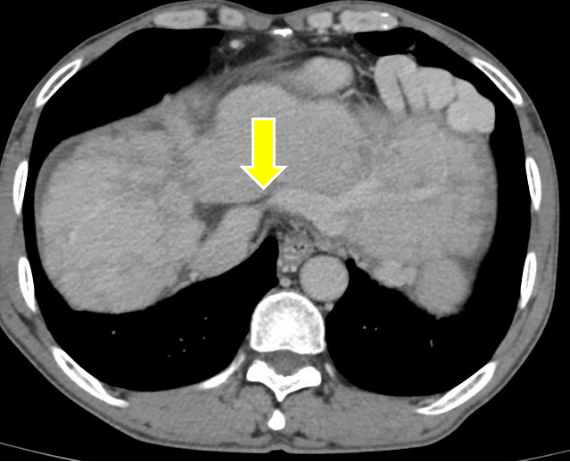

增强CT提示,李先生肝脏呈花斑样改变,三支肝静脉(肝右静脉、肝左静脉、肝中静脉)均异常,肝右静脉和肝中静脉未汇入下腔静脉,肝左静脉根部重度狭窄或有隔膜,继发心包旁大量侧支循环开放,提示布加综合征。

图1 增强CT提示肝左静脉流出端重度狭窄或闭塞